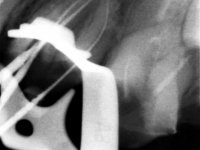

Male patient, 34 years old, non-smoker. Teeth 17 and 16 had extensive restorations with composite resin and placed intra-radicular posts. In the imaging examination, it was found that the endodontic treatment was not technically satisfactory, but had been asymptomatic for several years. The patient was rehabilitated with a 2-element bridge at 17 and 16 and 4 years later an abscess appeared in the apical area of 2.6. It had the 2.8 tooth included with a close relationship with the 2.7 root. During these 4 years there was no positional change of this tooth. After endodontic retreatment of teeth 27 and 26, an abscess appears again in the area of tooth 26, possibly associated with a root fracture. Given the history referred to in relation to tooth 26, it was considered a tooth with indicated extraction.

Teeth 17 and 16 were prepared for the fabrication of a 2-element Zr bridge. The impression was performed with a double mixing technique and a monolithic bridge in Zr was made in the laboratory. 4 years later, an abscess appeared in the apical area of tooth 26. It was decided to remove the bridge, remove the intra-radicular posts and retract the endodontic treatments of teeth 17 and 16. The removal of the bridge was carried out by making two cervical cavities. in the palatal area of the bridge and with a microluxator, disinsertion movements were performed. The intra-radicular posts were removed using fine drills and an ultrasound tip. The bridge was provisionally cemented and the patient was referred to a fellow endodontist for endodontic retreatment. After the retreatment, the intraradicular posts were placed again and the bridge was definitively cemented. One year later, a new abscess appears, possibly related to a root fracture. The bridge was sectioned between tooth 27 and 26 and tooth 26 was extracted and the crown of 27 was provisionally cemented. 3 months later, teeth 27 and 25 were prepared and a temporary bridge was made in dual polymerization resin. Then, an impression was made using the double mixing technique and a 3-element bridge in Zr was made in the laboratory. It was permanently cemented in the mouth with resin-reinforced glass ionomer cement.